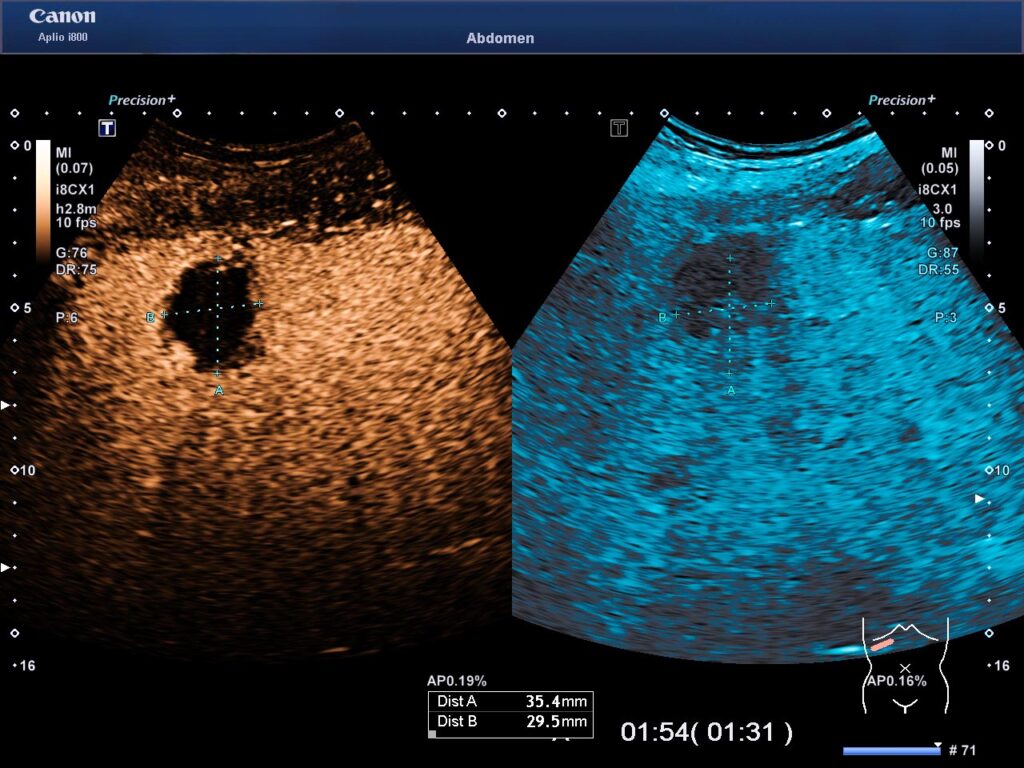

Ultraschallbild: Nach der Mikrowellenablation ist das Leberkarzinom aufgelöst (schwarz). In dem freien Raum kann Lebergewebe wieder nachwachsen.